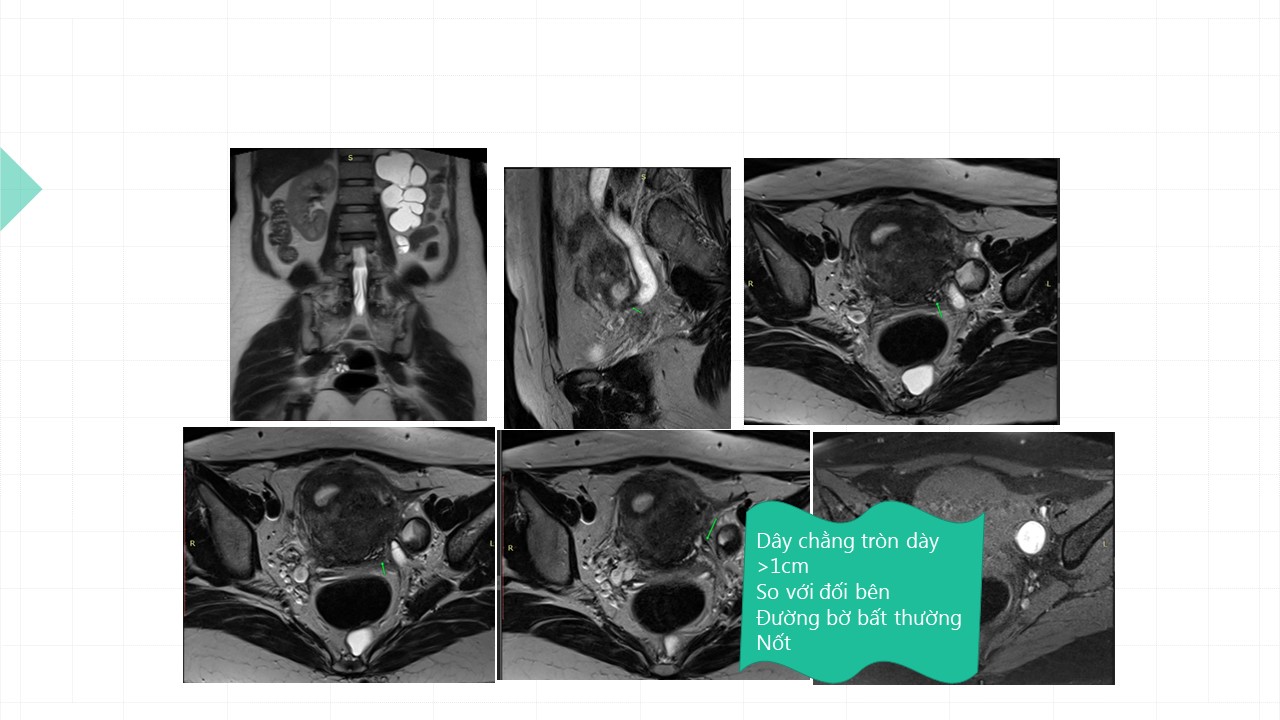

Vai trò cộng hưởng từ trong đánh giá lạc nội mạc tử cung